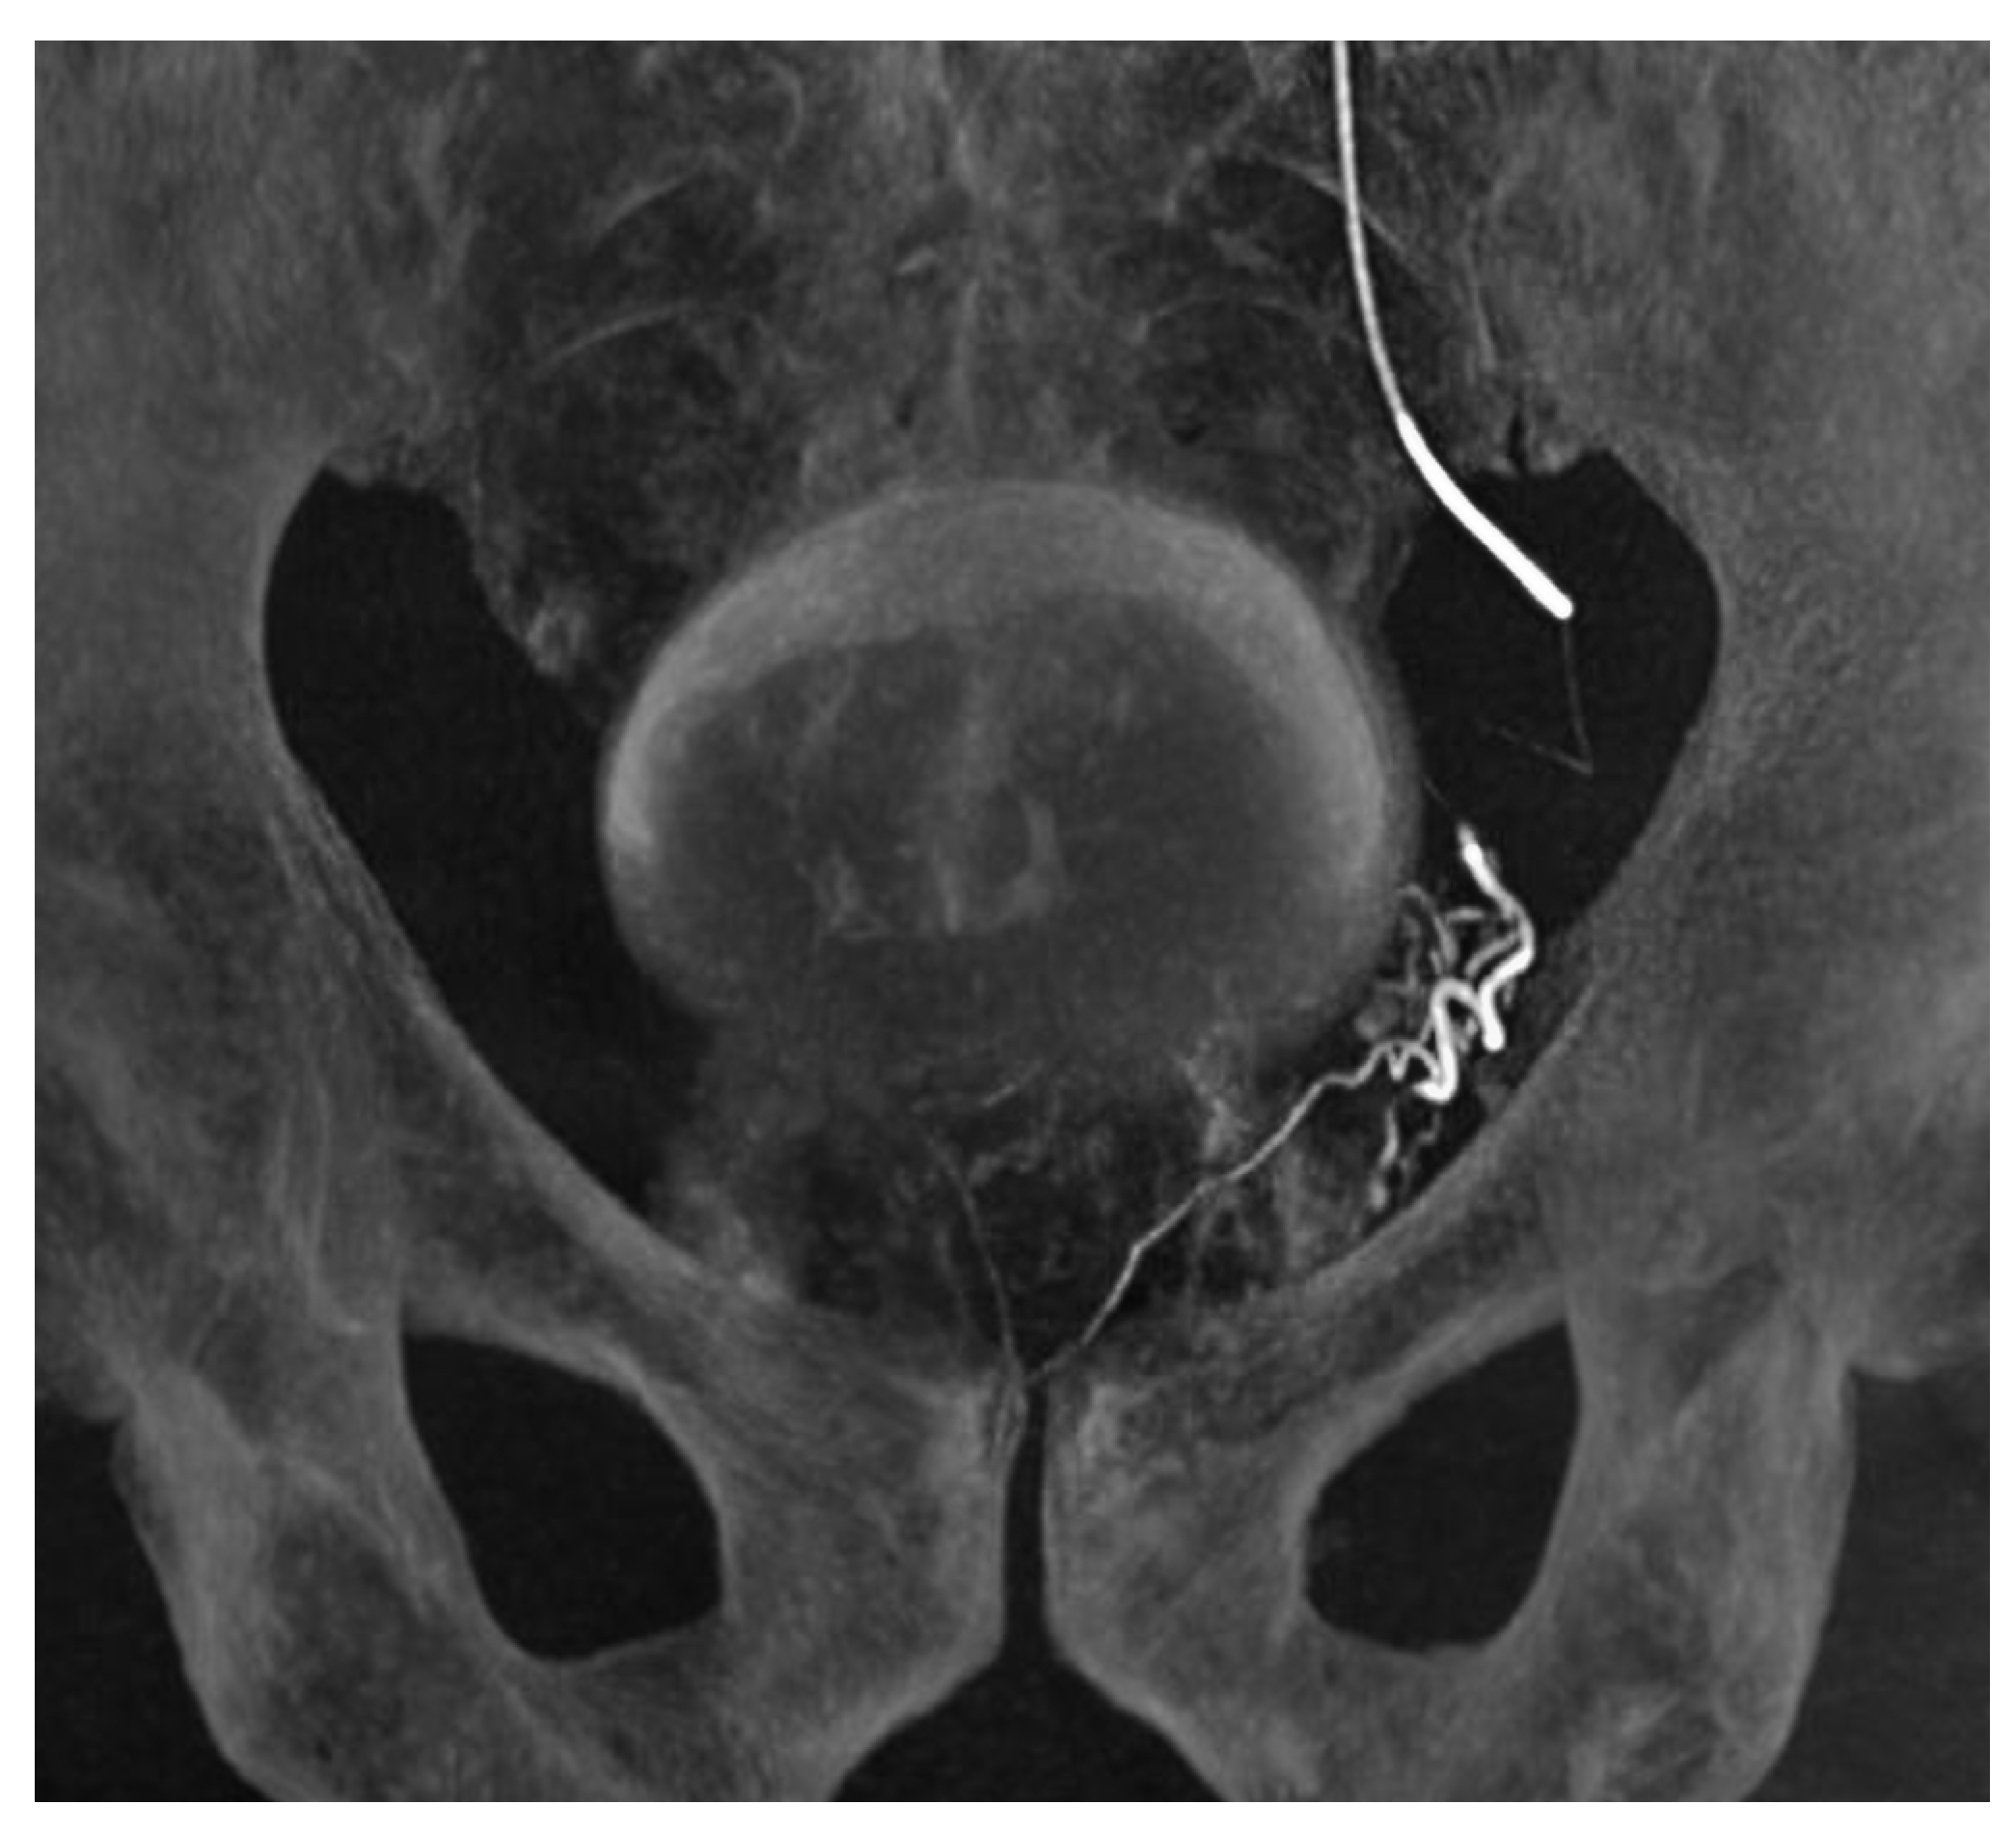

Figure 1.

Pelvic angiography of a 63-year-old male (case 1) undergoing prostatic artery embolization, with a catheter placed in the left internal iliac artery. The left prostatic artery is derived from the left obturator artery which is also is supplying an accessory pudendal artery to the penis.